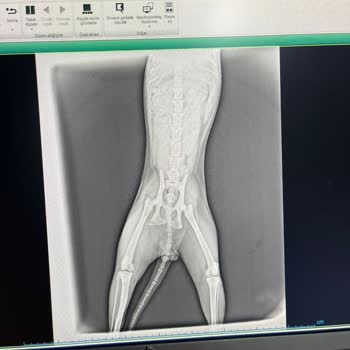

Ben kedimi (1.5 yaşında) balkondan düşme vakasıyla buraya getirdim. İlk müdahale olarak 2-3 tane ilaç enjekte ettiler. Daha sonra çok hızlı nefes alıp verdiğini söyleyerek oksijen vermek için kedimi benden emanet alıp saat 7 de röntgen için gelmemi söylediler. Gittiğimde ön sağ bacağında kırık olduğ...